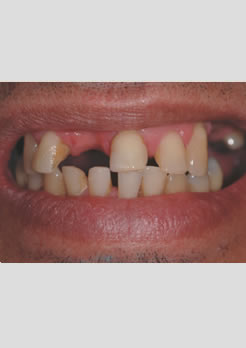

Antes – Paciente homem 45 anos, com perda de vários dentes e alteração no posicionamento dos dentes

Antes – são realizados exames pré operatórios como: exame de sangue, radiografias, tomografia computadorizadas em 3D, avaliação geral do estado de saúde do paciente e análise estética com Smile Design Pro

Instalação de 6 implantes na arcada superior com a técnica de carga imediata, com instalação da prótese em 48 horas